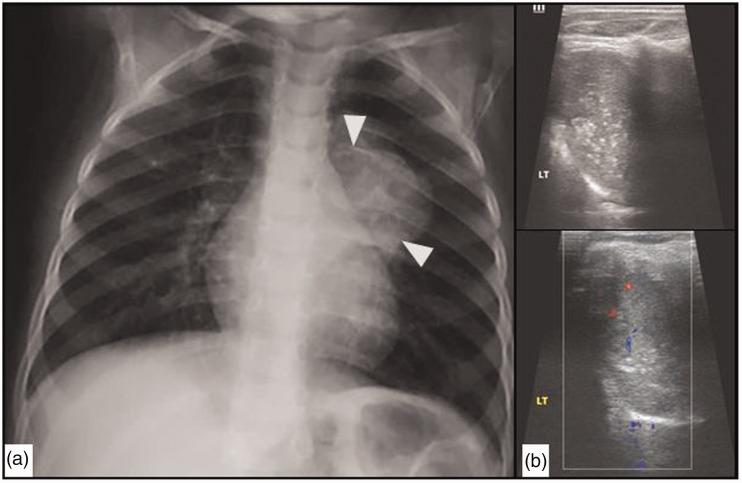

The purpose of this current pictorial review is to define the solitary round pulmonary lesion (SRPL), to familiarize with its prevalence in the pediatric population, and, moreover, to educate radiologists on its vast differential diagnosis and imaging manifestations. Furthermore, by highlighting valuable clues, it intends to assist radiologists efficiently partake in its diagnosis, work-up, and follow-up in order to narrow down the differential diagnosis by working alongside the clinician and combining clinical information, lab results, and radiological findings.

本次影像综述的目的是明确孤立性圆形肺病变(SRPL),使其在儿科人群中的患病率,此外,使放射科医生熟悉其广泛的鉴别诊断和影像学表现。此外,通过强调有价值的线索,旨在帮助放射科医生有效地参与其诊断、检查和随访,以便通过与临床医生合作并结合临床信息、实验室结果和影像学发现来缩小鉴别诊断范围。